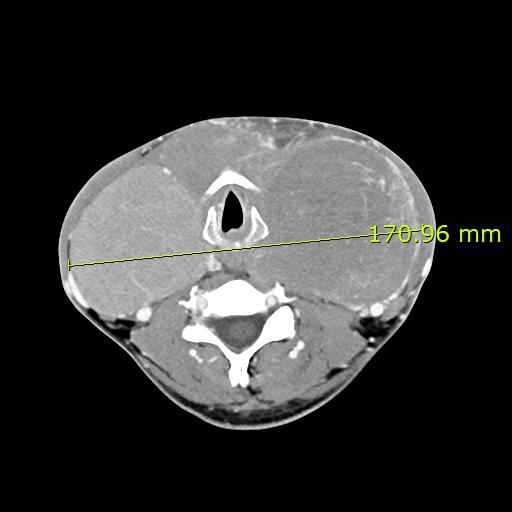

정부가 일으킨 의료대란으로 전공의들이 없던 2024년 가을이었습니다. 응급실의 연락을 받고 본 40대 남자 환자는, 그 헐떡거리는 숨소리에서 이미 심상치 않음을 느낄 수 있었습니다.

목을 감싸는 듯한 거대한 갑상선과 환자분의 창백한 안색은 그날 밤을 넘기기가 쉽지 않음을 짐작할 수 있었습니다.

CT에서 보이는 모양은 암처럼 보이지는 않았지만, 뭔가 모종의 병리가 있을 것으로 판단은 되었으나 야간 응급수술이었던 탓이 동결절편검사를 하지 못하고, 안전한 회복을 위해 기관절개술을 진행하고 수술을 마쳤습니다.

다음날 정식 CT판독은 thyroid lymphoma (갑상선 악성 림프종)의 가능성을 제시하였으며, 병상에서 잘 회복을 진행하던 일주일 쯤 뒤, 진단은 악성 림프종(lymphoma)로 최종 확진되었습니다.